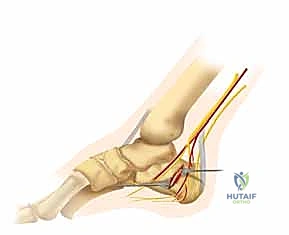

يتم وضع المريض على جانبه السليم. يقوم الدكتور هطيف بعمل شق جراحي دقيق على شكل حرف "L" على الجانب الخارجي للكاحل. يتم تصميم هذا الشق بعناية فائقة للحفاظ على التروية الدموية للجلد وتجنب إصابة العصب الربلي (Sural Nerve).

2. تقنية "عدم اللمس" (No-Touch Technique)

للحفاظ على حيوية الأنسجة الرقيقة (السديلة الجلدية)، يستخدم الدكتور هطيف أسلاك كيرشنر (K-wires) لرفع الجلد بعيداً عن مجال الرؤية دون استخدام مبعدات قاسية قد تدمر الأنسجة. هذه التقنية المتقدمة هي سر التئام الجروح السريع بدون نخر (Necrosis).